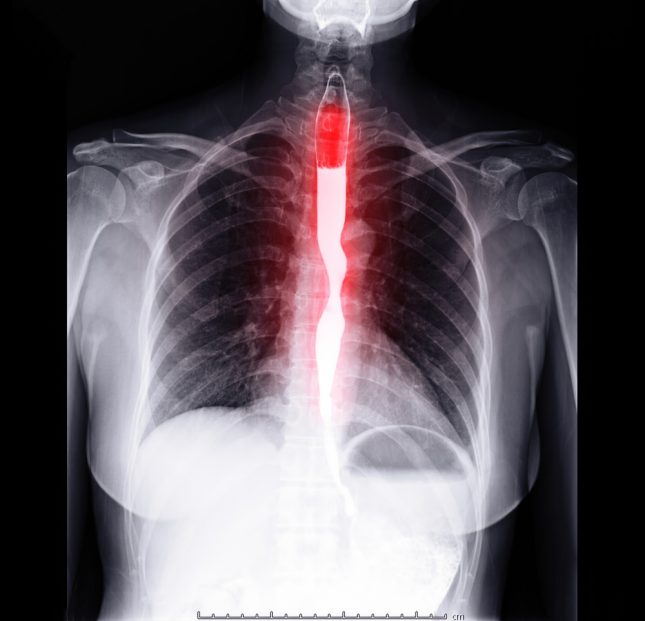

החזר קיבתי-ושטי (gastro-esophageal reflux disease – GERD) יכול לגרום למספר תסמינים בדרכי הנשימה העליונות ואף לשנות את הפיזיולוגיה של רירית האף (Nasopharyngeal mucosa). כבר זמן מה בספרות המקובלת, נחשבה אסתמה כגורם סיכון ל-GERD. כמו כן, אסתמה ונזלת אלרגית (allergic rhinitis – AR) מזוהות בדרך כלל כמחלה אחת בדרכי הנשימה, אשר מאוחדת בשל אפידמיולוגיה ופתופיזיולוגיה דומות. אף על פי כן, הקשר בין AR ל-GERD פחות ברור.

לסיכום, ייתכן של-AR מתאם חזק יותר עם GERD מאשר לאסתמה, אם כי אסתמה עלולה להגביר את הסיכון ל-GERD באמצעות מסלולים פתו-פיזיולוגיים משותפים עם AR.